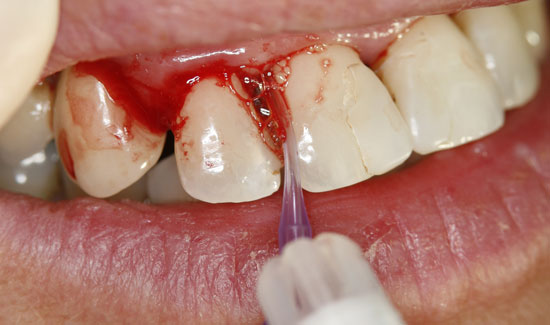

Fig. 3: Condition after ozone therapy. Chlorhexidine staining of the teeth

As an ozone gas source, we used Prozone, which, with the aid of plastic attachments, makes it possible to introduce ozone gas into the pockets in a pain-free manner. The local application of ozone gas was repeated three times, at weekly intervals. The patient was also made aware of necessary personal hygiene measures. Not only were we able to stop the bleeding, but we were also able to keep the degree of mobility of the teeth at a stable level (2) and reduce the measurable depth of the pockets.

The ozone gas generator from W&H (Prozone) is characterized by its ease of use and safety of application (preset tissue-compatible dosages in the indication areas of periodontitis and endodontitis). Prozone ensures a hygienic procedure during the gassing of the pockets thanks to its exchangeable plastic attachments (Perio tips or Endo tips). Treatment of pain is not necessary, as ozone displays pain-relieving properties (on slow-conducting C-fibres).